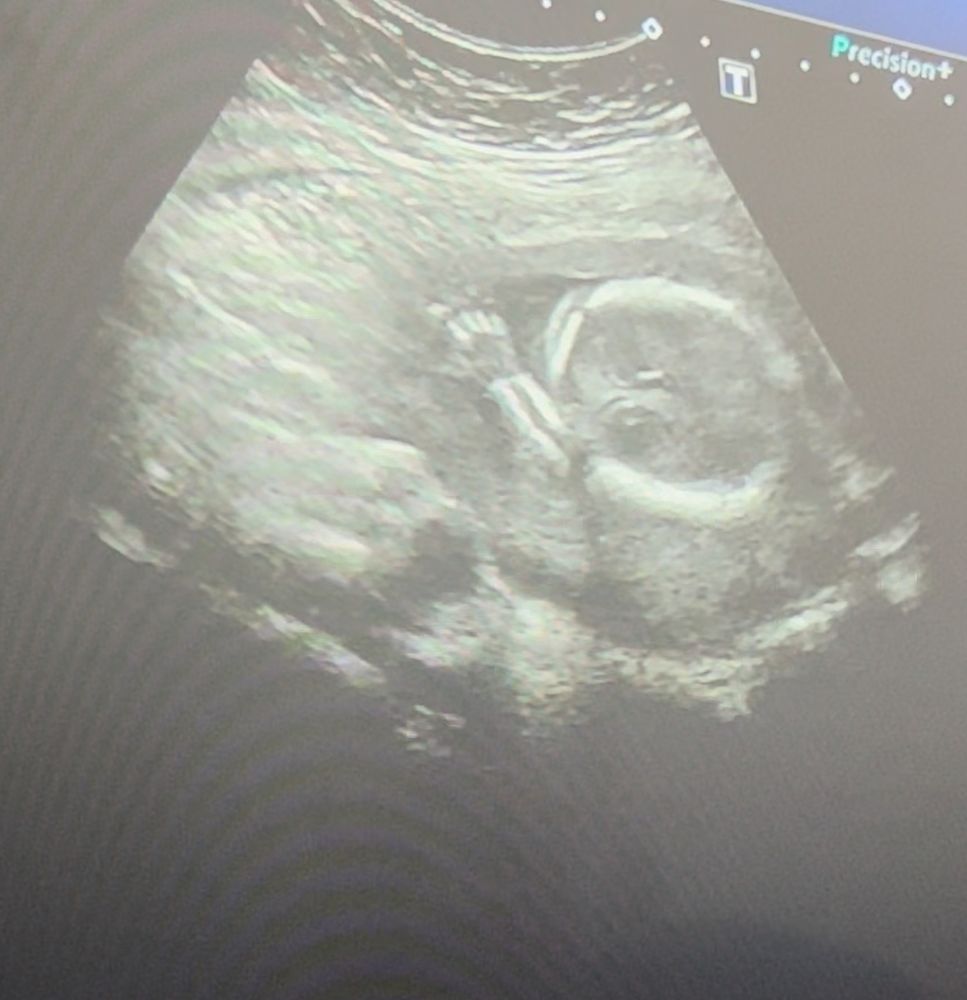

18 недель. УЗИ и стойкие мы 🩵🩷

Первое узи 😊 Толщина рубца посое кс